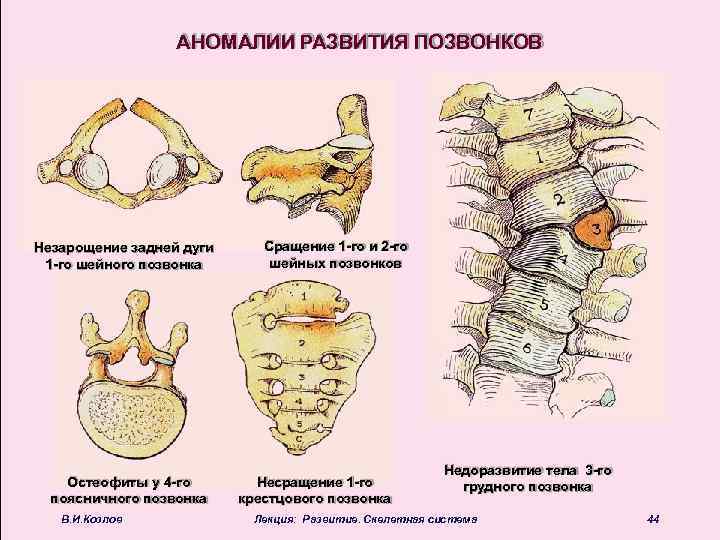

АНОМАЛИИ РАЗВИТИЯ ПОЗВОНКОВ Незарощение задней дуги 1 -го шейного позвонка Остеофиты у 4 -го поясничного позвонка В. И. Козлов Сращение 1 -го и 2 -го шейных позвонков Несращение 1 -го крестцового позвонка Недоразвитие тела 3 -го грудного позвонка Лекция: Развитие. Скелетная система 44